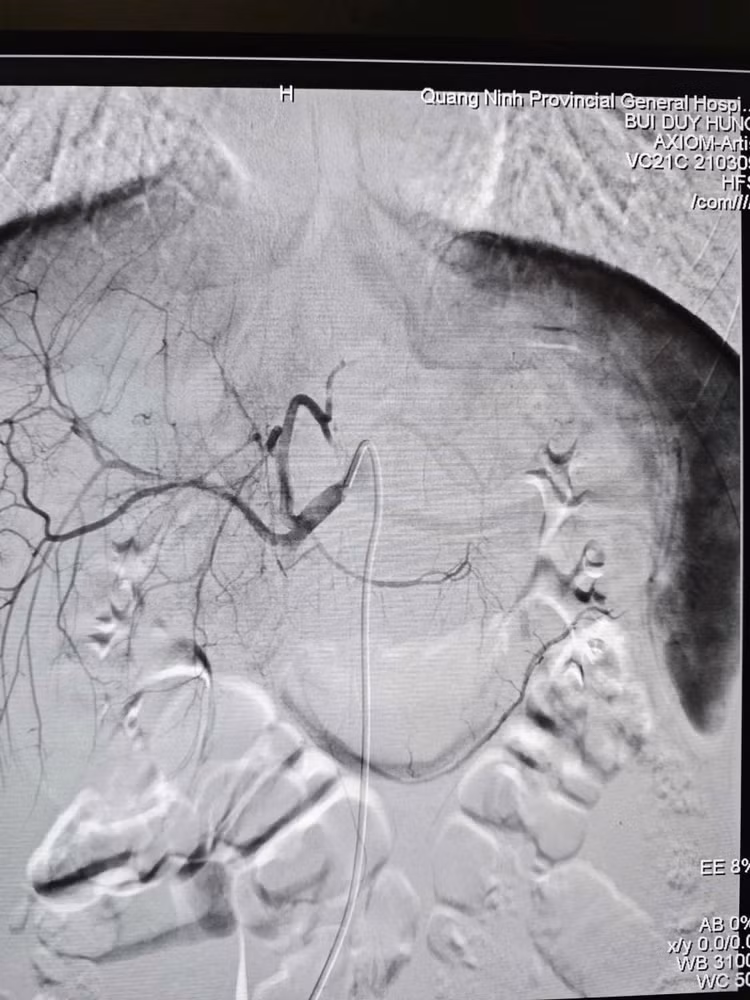

Ê-kíp can thiệp mạch do BSCKII Bùi Duy Hưng- Phó khoa Chẩn đoán hình ảnh – Điện quang can thiệp trực tiếp thực hiện. Ảnh BV

Khi vận chuyển người bệnh về tại cơ sở chính, ê-kíp Can thiệp mạch đã sẵn sàng mọi nguồn lực. Ngay khi tiếp nhận, nhận thấy bệnh nhân có dấu hiệu thiếu máu, các bác sĩ đã chỉ định truyền máu kịp thời trước khi can thiệp. Dưới sự hỗ trợ của hệ thống DSA hiện đại, ê-kíp bác sĩ đã luồn ống thông (Microcatheter) siêu nhỏ 1.9F tiếp cận siêu chọn lọc vị trí nhánh động mạch gan đang chảy máu và nút tắc bằng vật liệu chuyên dụng Spongel.

Hình ảnh sau nút mạch điều trị chấn thương gan, ổ chảy máu đã được nút tắc./Ảnh BV

Sau 60 phút, ca can thiệp thành công tốt đẹp, hình ảnh chụp kiểm tra cho thấy điểm chảy máu đã được cầm hoàn toàn. Huyết động bệnh nhân ổn định và được chuyển hậu phẫu theo dõi với tiên lượng phục hồi. Thành công của ca bệnh khẳng định hiệu quả của mô hình hoạt động đồng bộ, năng lực chẩn đoán tại chỗ nhanh, chính xác ngay từ đầu nhờ CT Scanner và nhân lực chất lượng làm chủ kỹ thuật nút mạch giúp xử trí chấn thương nhẹ nhàng, hiệu quả cao.